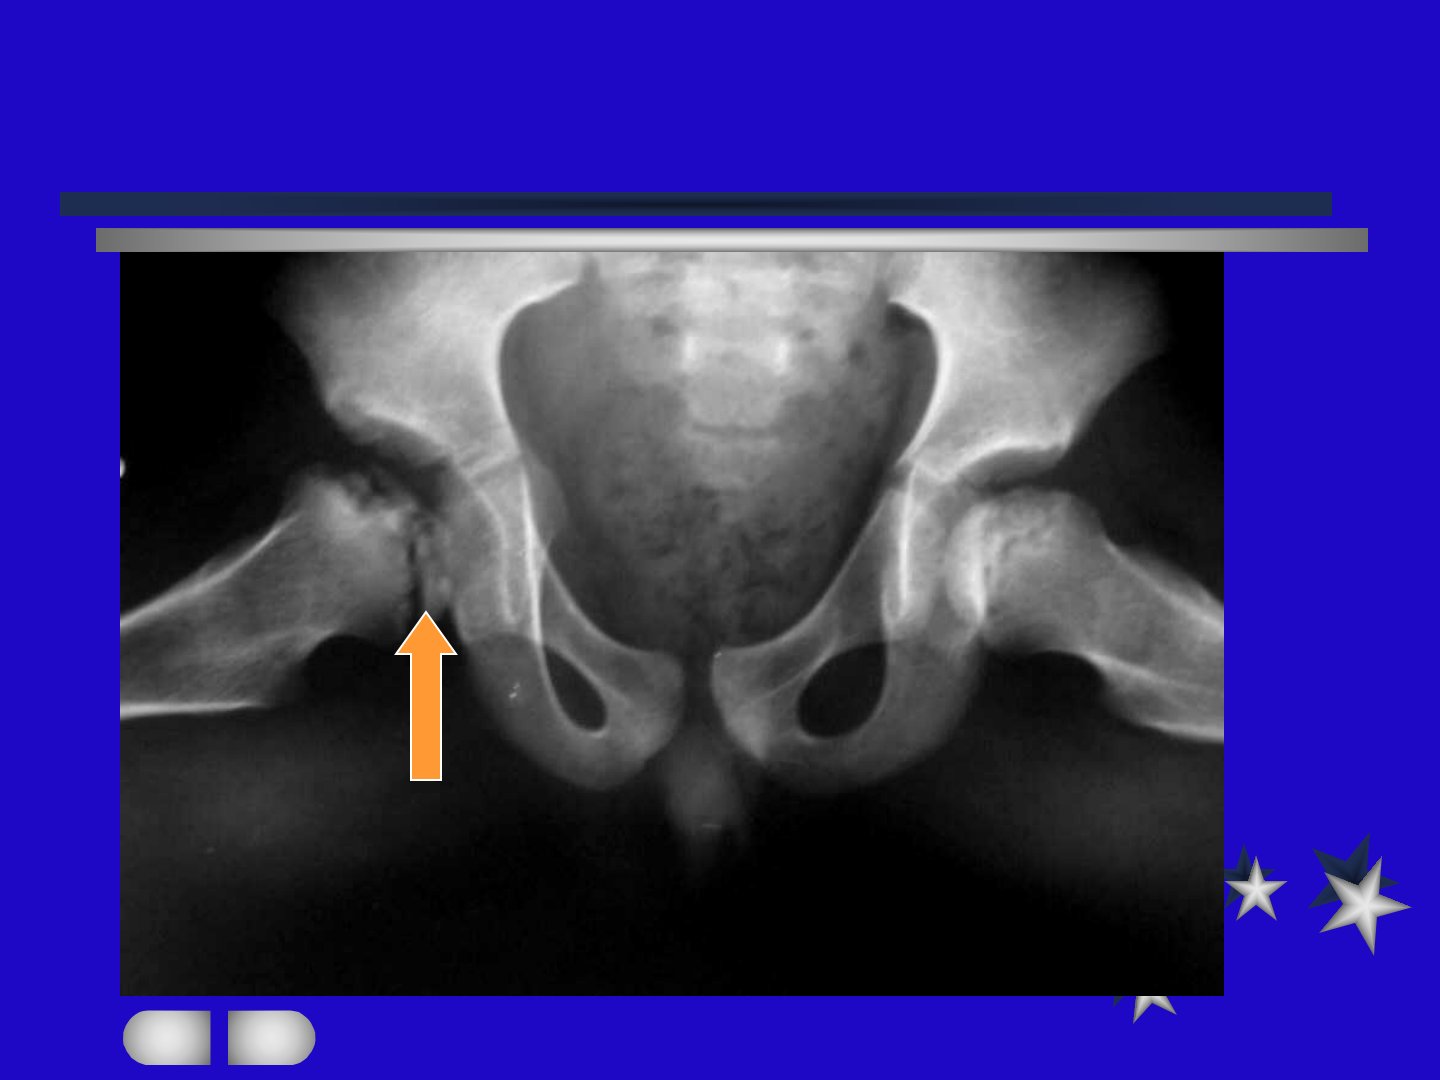

儿童股骨头缺血性坏死简称Perthes病1910年由Legg、Calve、Perthes分别描述多见于410岁男孩男女比例41双侧病例占10美欧发病率较高。该病真正致病原因尚未明确是世界骨科界研究热门课题之一。早期有炎症学说认为与骨感染有关但未得到病原菌证实也有学者提出该病与一过性滑膜炎关系密切。病因方面有学者提出动脉栓塞、骨髓内压增高、静脉瘀血等血管因素以及髋关节内压力增高、头血供不足等观点。病理上该病表现为骨骺多次缺血性梗死病程分为初期、缺血期、碎裂期、愈合期起病缓慢病程长有间歇性跛行与疼痛。临床表现包括下肢肌肉萎缩、内收肌痉挛等诊断依据病史、临床症状、X线等需与暂时性髋关节滑膜炎、髋关节结核等鉴别。治疗总原则是避免股骨头的机械压力、改善或恢复血循环手术治疗包括股骨上端截骨术等非手术方法采用特定位支架或行走石膏中远期随访优良率在90以上。